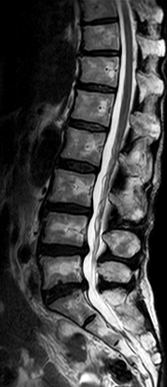

在磁共振领域,深度学习技术对图像进行降噪、上采样、减轻振铃伪影的处理,带来了清晰且细节丰富的图像。

过去,高分辨率图像的获取往往伴随着漫长的扫描时间,这影响了图像获取的效率,对于危重疾病的快速诊断是一大挑战。然而,PIQE技术的出现彻底颠覆了这一局面。此次发布的全新3T磁共振Galan Supreme,搭载全新的自研磁体和梯度线圈,并深度融合PIQE技术,可以实现在不增加扫描时间的前提下,轻松获取到高分辨率的图像,为临床带来了兼具高效与高质量的影像体验。